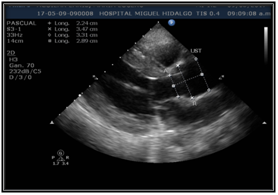

We present the case of a 37-year-old woman who began her cardiovascular history with the detection of an indeterminate heart murmur in the first pregnancy, which was not followed up. In the second pregnancy, she presents severe preeclampsia, since then with chronic arterial hypertension, in follow-up a significant difference in blood pressure between both upper extremities is also detected. She presented deterioration in the functional class and hypertensive uncontrol, so he went to our hospital for assessment by cardiology. To auscultation, with murmur of decreasing holodiastolic aortic epicenter, intensity III / IV irradiated left sternal border; Flint Austin murmur present. Celler carotid pulses, right subclavian path with systolic thrill; intense palpable pulse under right clavicle and supra sternal hollow. Upper limbs with asymmetrical trophism, blood pressure right arm 240/80mmHg, blood pressure left arm 200/80mmHg. Lower limbs with a right lower femoral pulse. Electrocardiogram with sinus tachycardia. (Figure 1)

Transthoracic echocardiogram was performed in which trivalva aortic valve was observed with limited coaptation of the cusps that produces severe regurgitation, vena contracta of 6 mm, EROA of 0.5 cm2, aortic root of 36 mm, ascending aorta 35 mm, LVED 51mm, LVEF 59%. (Figure 2 & Figure 3) Severe aortic regurgitation was diagnosed, with Takayasu arteritis as probable etiology. Thoracic angiotomography and angiography were performed, showing areas of stenosis in the left carotid and the left subclavian artery. (Figure 4–7) The final diagnosis was severe aortic insufficiency secondary to dilation of the aortic root due to Takayasu's arteritis by Ishikawa criteria. Treatment with aortic valve replacement with mechanical prosthesis was decided.